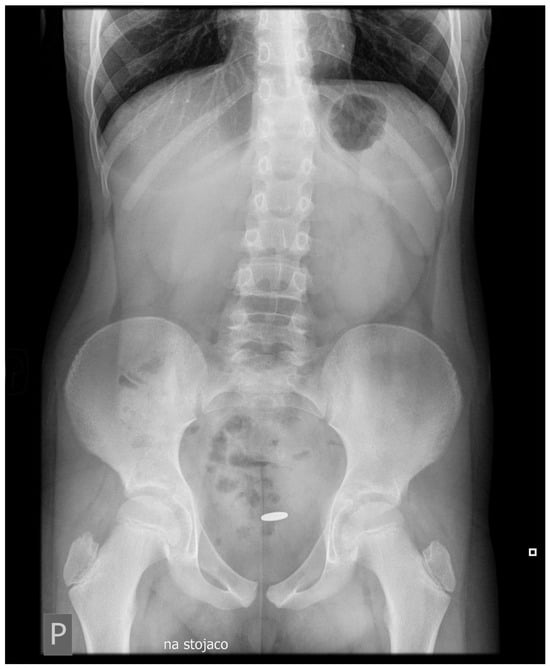

Abstract

1.1. Case Presentation

1.2. Investigations